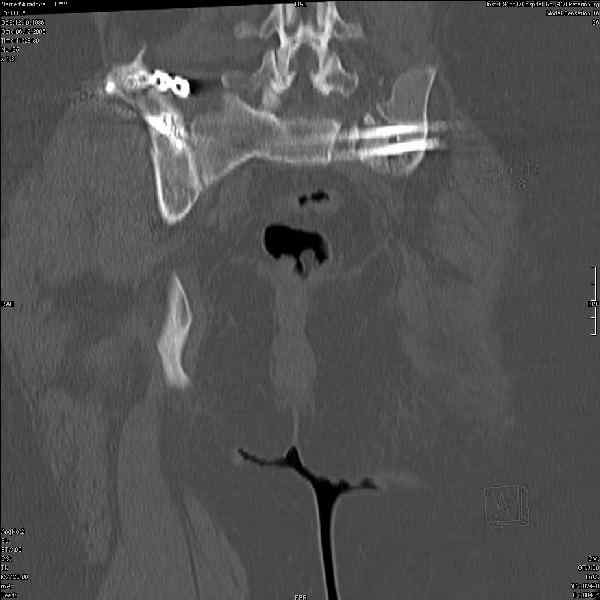

Здравствуйте, коллеги. Какие будут мнения по поводу лечения представляемой больной?

Молодая девушка 19 лет, травма 1 год назад, тогда же прооперирована.

В настоящее время имеются ноющие боли в области крестца слева, нарушение походки, ощущение неуверенности, слабости в левой нижней конечности, неврологически -непостоянные парестезии в левой нижней конечности. Ходит с дополнительной опорой, страдает от ожирения.

Какова по вашему будет оптимальная тактика в отношении несращения крестца? Замена винтов на более длинные с коррекцией их положения+ туннелизация зоны нестращения, открытое вмешательство с костной аутопластикой или еще какие варианты?

В приложении снимки при поступлении и послеоперационные год назад.

Могу сказать одно: миграция винтов и нестабильность синтеза левого подвздошно-крестцовогоо сочленения очевидна.